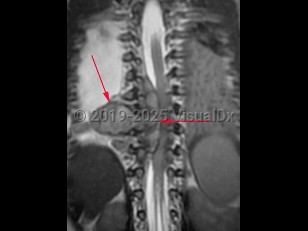

Neuroblastoma is a neuroendocrine tumor that arises from neural crest cells. It is the most common solid tumor of infancy and childhood; typical age of onset is less than 3 years old. The adrenal glands are the most frequent site of origin, but this tumor can be found anywhere along the sympathetic nervous system chain including the neck, chest, abdomen, or pelvis. Presenting symptoms depend on the site of origin and areas of metastasis if present but may be nonspecific including fatigue, fevers, anorexia, abdominal pain, or joint or bone pains. Less common symptoms include weakness, ataxia, chronic diarrhea, hypertension, or shortness of breath. The presence of Horner syndrome or opsoclonus-myoclonus syndrome in children should prompt evaluation for this type of tumor. Rarely, neuroblastoma may be an incidental finding on radiology.

Treatment and prognosis depend on whether the tumor is low, intermediate, or high risk. Metastases are associated with a high mortality rate.